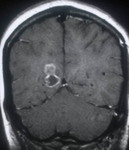

Calcified stage - neurocysticercosis: MRI scan of multiple calcified lesions in a patient with neurocysticercosis

From the personal collections of Dr Christina Coyle and Dr Maheen Saeed; used with permission